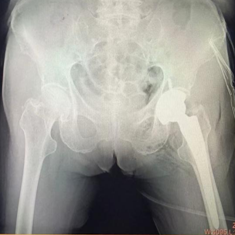

在手术团队、麻醉科及手术室的精密配合下,手术历时约一小时顺利完成。术后 X 光片显示假体位置精准,效果理想。

更令人欣喜的是患者的术后反应:术后第二天,在医护人员指导和协助下,这位 80 岁的患者已能顺利下床站立,并借助助行器尝试行走。